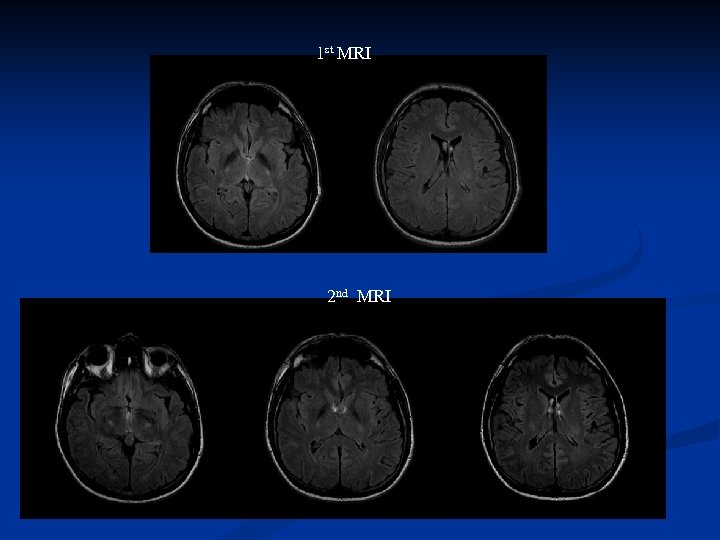

Follow up MRI was performed in nine ALS patients, four of which had distinct signal changes in the PLIC. Three of these patients deteriorated or developed definite ALS in the progress of the disease, thus changing diagnosting category according to the revised El Escorial criteria. The follow up examination disclosed that the increased T 2 FLAIR signal change got either more accentuated or more extended craniocaudally to the corona radiata/centum semiovale and the crus cerebri , demarkating the CST

Follow up MRI was performed in nine ALS patients, four of which had distinct signal changes in the PLIC. Three of these patients deteriorated or developed definite ALS in the progress of the disease, thus changing diagnosting category according to the revised El Escorial criteria. The follow up examination disclosed that the increased T 2 FLAIR signal change got either more accentuated or more extended craniocaudally to the corona radiata/centum semiovale and the crus cerebri , demarkating the CST

1 st MRI 2 nd MRI

1 st MRI 2 nd MRI

1 st MRI 2 nd MRI

1 st MRI 2 nd MRI